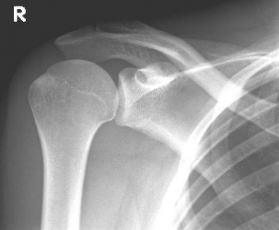

Abbildung2Abbildung1

left: X-ray image of an omarthrosis

right: X-ray of a healthy shoulder joint

X-rays can be used to reliably diagnose the extent of joint wear. In the case of severe osteoarthritis, for example, the joint space and the formation of jagged edges (osteophytes) can be detected. If additional damage to the tendons of the shoulder (rotator cuff) is suspected, ultrasound examination (sonography) or magnetic resonance imaging (MRI) can help clarify the situation.